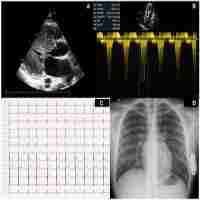

| Abstract | Background There is only limited experience with wearable cardioverter-defibrillators (WCD) in pediatric patients. We report on the successful application of a WCD in an adolescent patient with hypertrophic cardiomyopathy and myocardial bridging. Case presentation A 15-year-old girl presented with a history of recurrent syncope, dyspnea, and vertigo with exercise. Diagnostic work-up revealed non-obstructive hypertrophic cardiomyopathy and signs of myocardial ischemia with exercise. Given this high-risk constellation, the patient was scheduled for prophylactic implantation of an implantable cardioverter-defibrillator (ICD). One month after initial presentation and days prior to the planned ICD implantation, the patient collapsed during an episode of sustained ventricular tachycardia (VT) while running. VT was terminated by WCD shock delivery. Following this event, computerized tomography scan revealed myocardial bridging of the left anterior descending coronary artery causing a 90% stenosis in systole. After coronary surgery, life threatening arrhythmias have not recurred, but due to progressive heart failure, the patient underwent successful heart transplantation after 2 years. Conclusions The reported case highlights the importance and applicability of WCDs and the potentially malign nature of myocardial bridging in pediatric high-risk patients. |